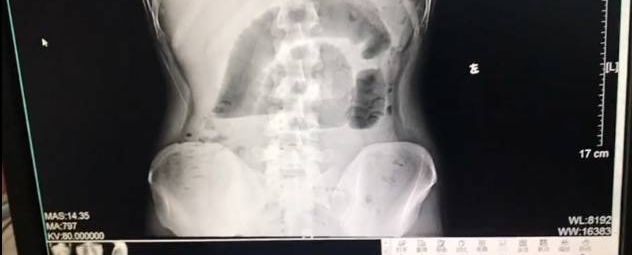

广州一名24岁的小伙子,因为早上太饿,“囫囵吞枣”一口气吃下三个茶叶蛋,基本没有怎么咀嚼,没想到吃下去的茶叶蛋变成了“凶器”,造成了小肠梗阻,不得不住院花一万多块钱做手术取出。网友纷纷评论:这算是史上最贵的茶叶蛋了吧,3个一万。

茶叶蛋在我们印象中,基本没有囫囵吞下去的可能,都要嚼碎来吃。但是小伙估计饿极了,就生吞了。那有人会说,平时我们吃鸡蛋都会被胃液腐蚀掉,怎么可能整颗鸡蛋不消化堵到小肠处呢?原来我们的胃是持续分泌胃酸的,其基础的排出率约为最大排出率的10%,且呈昼夜变化,入睡后几小时达高峰,清晨醒来之前最低。

鸡蛋蛋白本来就属于不易消化的食物,加上小伙子一口气吞三颗鸡蛋,未经消化的整颗鸡蛋堵到小肠,引起肠梗阻就不难理解了。善待我们的身体,面对美食细嚼慢咽绝对是必须的。